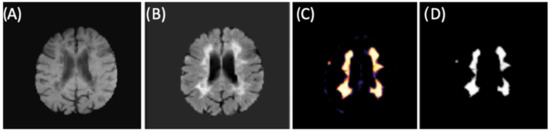

The final training model obtained from the second CNN (as described in Materials and Methods 2.3 and in Figure 2) was used for brain lesion detection, where convolutional blocks were applied to the FLAIR input. From binary mask (outputs), we could detect lesions within new individuals (images) from our test group. Figure 9 shows an example of lesion segmentation on a patient from the test group.

Figure 9.

CNN example for lesion segmentation. (A) T1-w image after preprocessing and brain extraction. (B) FLAIR image after preprocessing and brain extraction (second CNN input). (C) Lesion memberships. (D) Binary mask by thresholding the probabilistic memberships.

Because lesion volume definition is a relevant metric for assessing disease evolution and monitoring treatment, we determined volumetric quantification of the brain lesion by counting the detected voxels from the binary mask (CNN output). After volumetrically quantifying the lesions of all patients from the test group, we obtained a mean value of 17,582 mm3; Figure 10 shows an example where the segmentation was performed on all slices and volumetrically represented.

Figure 10.

(A) Images for identification and segmentation of sclerotic lesions. (B) Brain with lesion volumetric representation. (C) Segmented volumetric lesion.